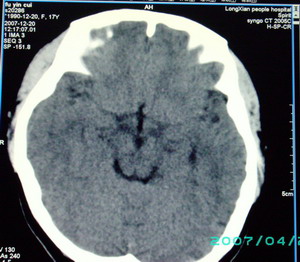

以下是引用九目段在2007-12-24 14:55:00的发言:[br]1,年轻女性[br]2,ct表现:左侧脑室三角区可见一不规则小明显强化的结节,中央见小低密度,侧脑室无扩张。[br]分析:[br]常见的有三种肿瘤好发三角区:[br]1,脉络丛乳头状瘤,好发于年轻者,明显强化,实性,分泌脑脊液,常伴有侧脑室扩大,肿瘤较小可以脑室扩大不明显,不能排除,但小结节尚不易形成坏死腔。[br]2,室管膜瘤,好发于儿童及青少年,明显强化,易坏死,大时伴脑室扩张。[br]3,脑膜瘤,明显强化,圆形,界请,无脑积水,一般不坏死。[br]诊断:[br]左侧脑室三角区结节,考虑室管膜瘤可能性大,不排除脉络丛乳头状瘤和脑膜瘤(因病史较长)。[br][br][本贴已被 九目段 于 2007-12-24 15:13:35 修改过]